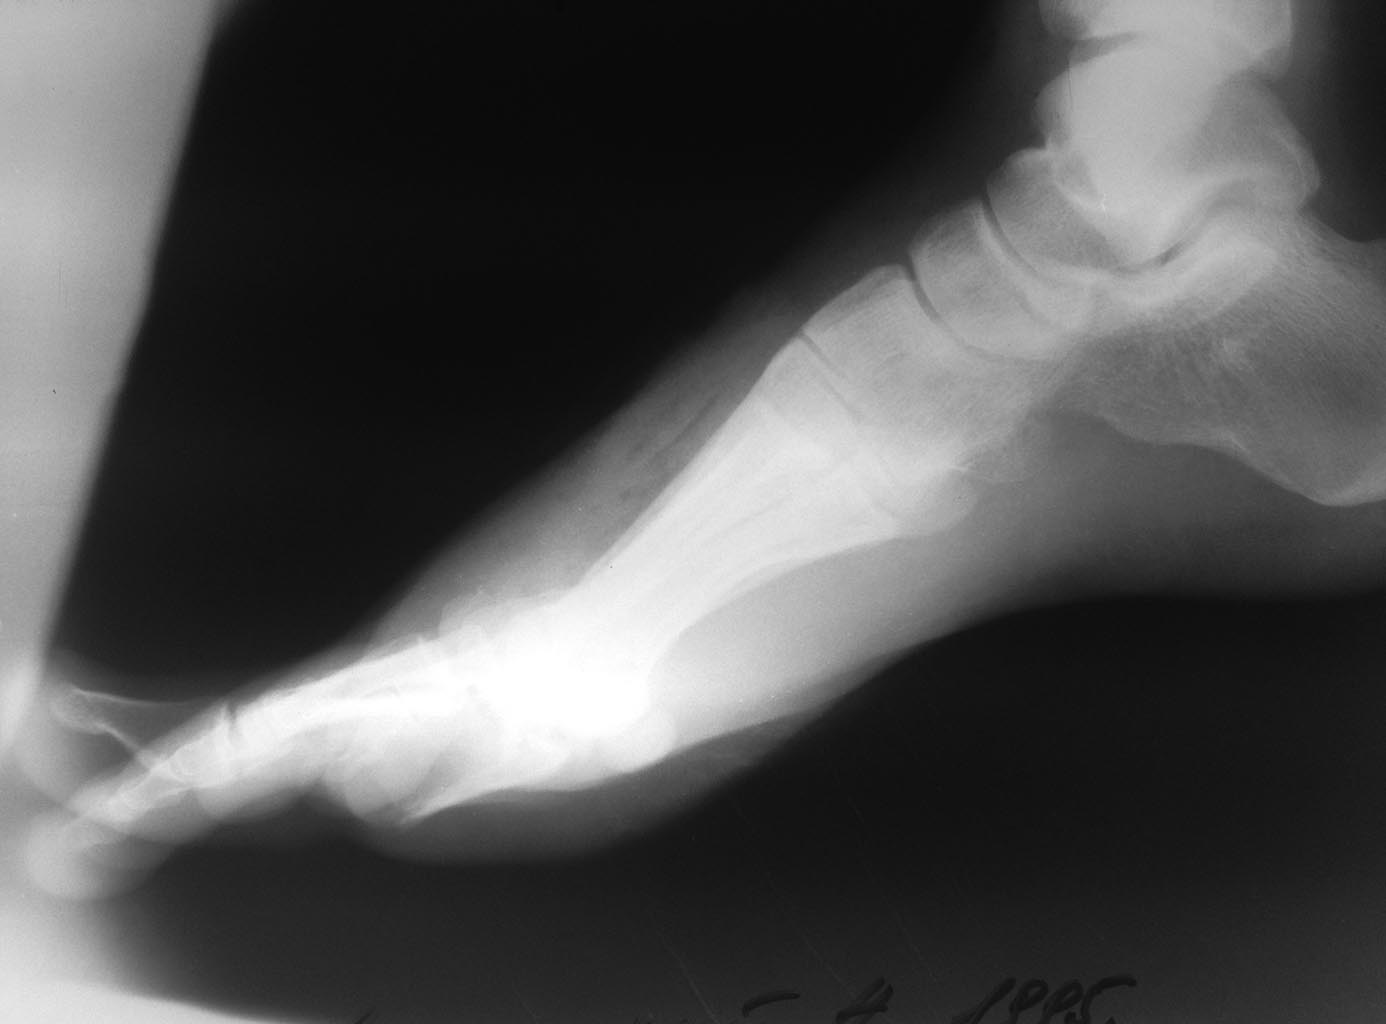

[Ortho] Травма стопы тяжелым предметом - нужен совет

Имя     : image2.jpg